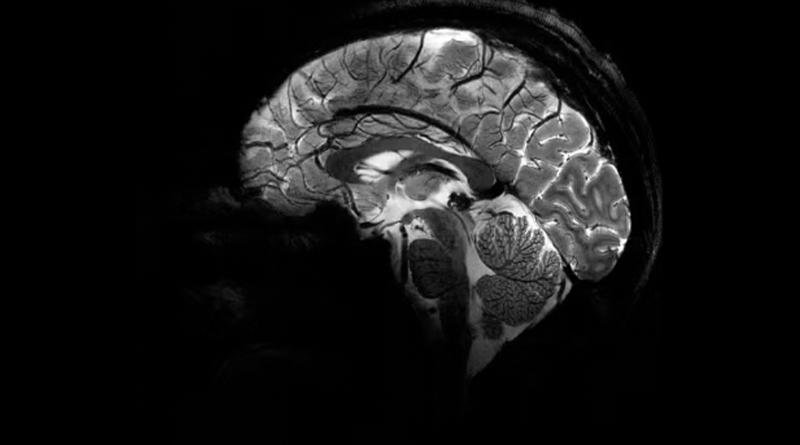

Imagem do Iseult com um campo magnético de 11,7 teslas. — Foto: Reprodução/Comissão de Energia Atômica da França (CEA)

A Comissão de Energia Atômica da França (CEA) divulgou nesta terça-feira (2) as primeiras imagens do cérebro humano feitas pelo aparelho de ressonância magnética mais potente do mundo. De acordo com os responsáveis pelo projeto, o scanner atingiu um nível de precisão jamais visto, algo que pode ser decisivo para detectar doenças.

O campo magnético criado pelo scanner é de 11,7 teslas. Essa potência permite que a máquina escaneie imagens 10 vezes mais precisas do que os aparelhos normalmente utilizados em hospitais – cuja potência geralmente não supera os três teslas.

Em uma tela de computador, Vignaud comparou imagens tiradas por esse poderoso scanner, apelidado de Iseult, com imagens de uma ressonância magnética normal.

“Com essa máquina podemos ver os pequenos vasos que alimentam o córtex cerebral, ou detalhes do cérebro que eram quase invisíveis até agora”, detalha.